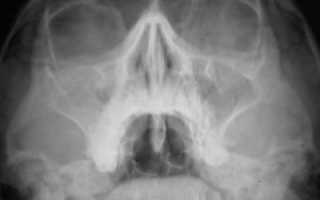

На рентгеновских снимках чаще всего можно увидеть субтотальное затемнение. Затемнение гайморовых пазух обычно появляется в двух нижних третях – обычно это воспаленная слизистая оболочка. Затемнение проявляется обычно при огромном скоплении жидкости или гноя в полости.

Рентгеновская проекция очень четко показывает решетчатые лабиринты, которые забиваются жидкостью наравне с пазухами. На рентгене лучше различается нижняя доля гайморовых пазух.

Носоподбородочная проекция лучше показывает нижние части обеих пазух, чем подбородочная проекция. Решетчатый лабиринт чрезвычайно плохо обозревается при любой проекции.

Затемнение гайморовых пазух выявляется с помощью рентгена и определяется даже врачом-рентгенологом. При появлении тени на снимке врач может предположить гайморит, синусит и прочие подобные заболевания. Рентгенографию назначают для выявления отека, присутствия гнойных масс или воспаления оболочки.

Рентгенограмма показывает наличие посторонних образований в пазухах, и от этого следует наличие какого-либо заболевания.

Пациентка Олеся, 21 год. Девушка пришла в больницу с жалобами на кашель, насморк и затрудненное дыхание, головные боли. Нос был заложен около трех недель. Рентгенография показала субтотальное затемнение гайморовых пазух.

Исходя из результатов обследования, был поставлен диагноз: гайморит (воспаление оболочек гайморовых пазух). Было назначено следующее лечение: Санорин или Тизин, Долфин или Маример, Диоксидин 1% или Хлоргексидин 0,05%.